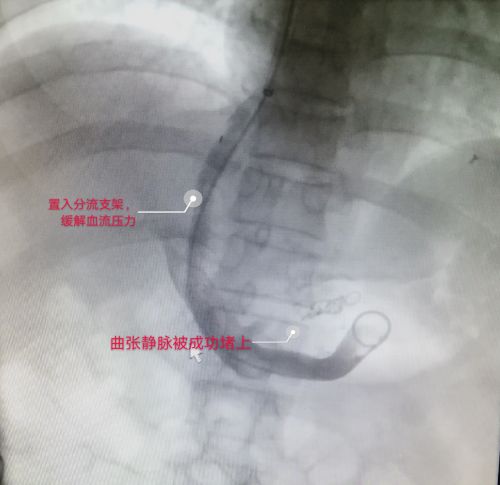

进一步检查后,王松被确诊为肝硬化引起的食管胃底静脉曲张,需尽早接受TIPS手术(经颈静脉肝内门体分流术)。手术需局部麻醉,医生担心王松不能配合,组织专家讨论病情,并制定了周密的手术方案和风险预案。

经过积极的内科治疗,待病情趋于稳定后,9月9日,龙林等医护人员为王松施行手术,手术历时2.5小时顺利完成。术后,王松的病情得到控制,精神状态好转,手术当天就可以下床活动,三天后康复出院,只在脖子上留下一个针眼大的穿刺口。

TIPS手术是从颈部穿刺进入肝内血管,置入支架,在肝脏内打造一条人工通道,从而降低血流压力,是治疗门静脉高压症合并静脉曲张破裂出血的重要介入技术,具有创伤小、适应症广、成功率高、疗效可靠等优点。应用这一技术可控制分流道的大小、适应不同个体需要,从而避免分流过度、降低肝性脑病的发生率。